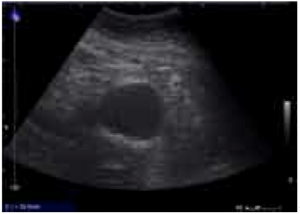

If a patient with a known history of AAA arrives unstable with symptoms consistent with rupture, no confirmatory diagnostic tests are necessary and the patient should be transferred to the OR expeditiously. Most patients, however, will require bedside imaging to confirm the diagnosis. Bedside ultrasound has emerged as the test of choice in this case. Ultrasound has a sensitivity of 98% in fasted patients undergoing screening, and while bowel gas and body habitus can hinder the exam, this is less of an issue in imaging the larger aneurysms that are likely to present ruptured. To obtain images of the aorta, a low frequency curvilinear probe is used. The probe is placed in the midline in the high epigastrium, and, using the liver as an acoustic window, gentle steady pressure is applied to displace bowel until the spine is visualized. The aorta will be seen as a round, hypoechoic structure on the patient’s left. (Figure 2) The sonographer should attempt to scan throughout the length of the aorta to the bifurcation (typically at the umbilicus), and should also obtain a sagittal view. Importantly, the diameter is measured from outer wall to outer wall, with > 3.0 cm being abnormal. If ultrasound is not available, a cross table lateral X-ray may show an AAA in up to 67% of cases. (Figure 3)

Figure 2: On the left, a normal sized Aorta, IVC and vertebra are labeled. On the right, a nearly 6 cm AAA is visualized. Images obtained from Dean AJ, Ku BS. Abdominal Aortic Aneurysm. Retrieved from: http://www.sonoguide.com/abdominal_aortic_aneurysm.html